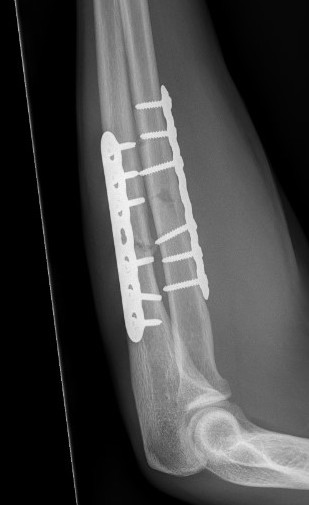

ORIF with DCP plates

Fixation with DCP plates